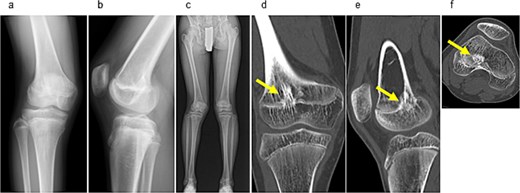

Examination revealed full range of motion in the affected knee (0–140°) and no pain during walking. Spinal malleolar distance assessment showed a leg length discrepancy of 30 mm (shorter right limb). Radiography showed valgus alignment with a femorotibial angle (FTA) of 162° on the right leg and 172° on the left (Fig. 1a–c). CT revealed early epiphyseal closure of the distal femur, indicating physeal bar formation near the posterior cortical bone (Fig. 1d–f). Accordingly, physeal bar resection was planned.

Preoperative radiographic and CT findings. (a) Anteroposterior radiograph of the right knee. (b) Lateral radiograph of the right knee. (c) Full-length standing anteroposterior radiograph of the lower extremities showing valgus deformity (femorotibial angle: right, 165°; left, 172°). (d) Coronal CT image. (e) Sagittal CT image. (f) Axial CT image showing early epiphyseal closure of the distal femur caused by a physeal bar (arrow), located adjacent to the posterior cortical bone.